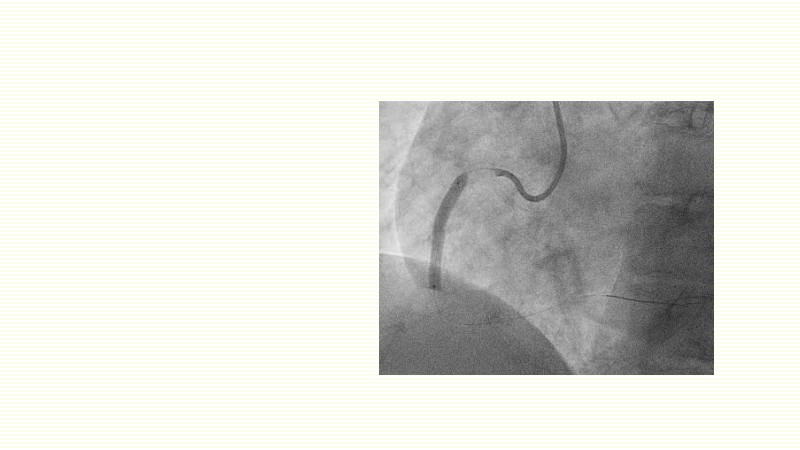

This EuroPCR 2025 session challenges the conventional approach to bifurcation PCI and dissection management. Learn why drug-coated balloons (DCB) may offer better long-term outcomes in cases where stents fall short, how DCBs can simplify bifurcation strategies, and why it’s time to rethink which dissections really need stenting. Through data, case examples, and clear decision-making insights, you'll gain the confidence to broaden your DCB practice where it truly matters.

- To reflect on when to use drug-coated balloons and stents

- To evaluate which dissection to leave and which to stent